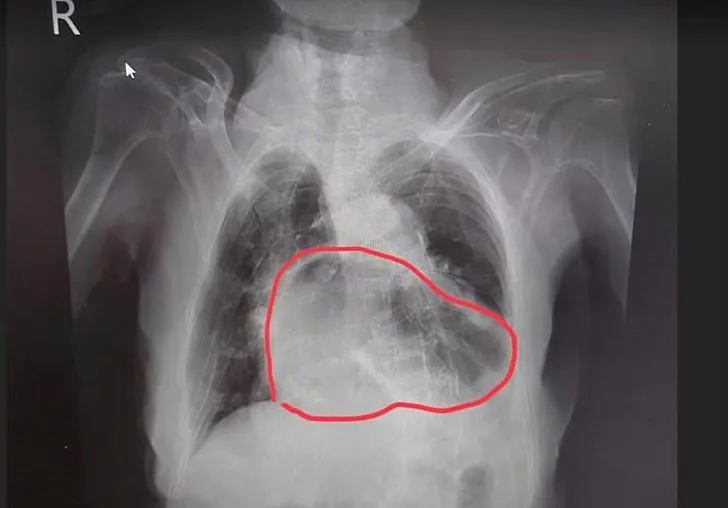

咳嗽

X光

胃疝脫

呼吸不順

胃食道逆流

呼吸道疾病

姜冠宇